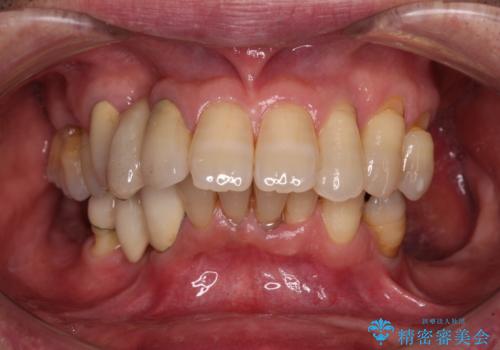

- 以前入れ歯を製作したものの、装着感が悪く使用できなかったとのことで来院された患者様です。

インプラントによる治療プランも提案しましたが、インプラントは避けたいとのご希望であったため、入れ歯による補綴治療を行うこととしました。

自費治療の義歯は装着感がとても良いですが、急に入れ歯を装着すると、異物感が強く継続使用できなくなるため、仮歯の期間中に保険治療での義歯を装着してもらい、口腔内を義歯に慣れさせるようにしました。